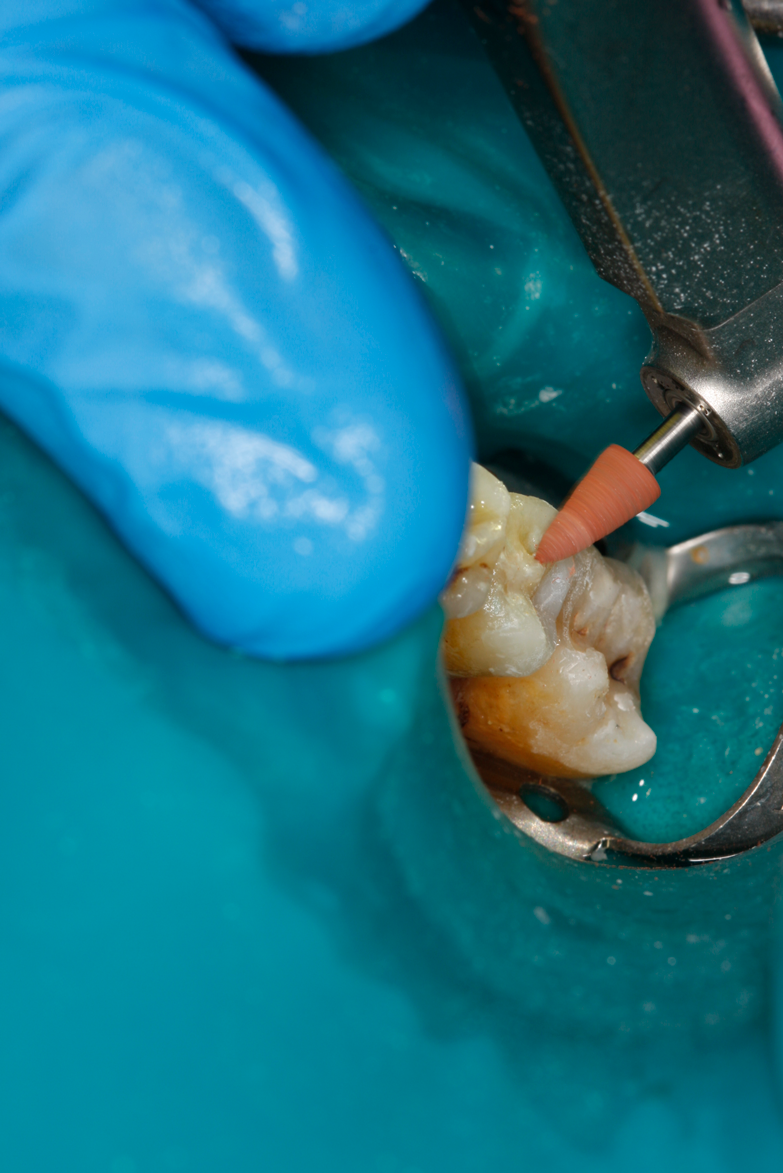

Fig 35. Injection filling of cavity preparation with dual-cure bulk-fill flowable composite to a slight overfill.

Figure 35

Fig 36. Injection overfill smoothed with a brush. At this step, it is important not to disturb the margins.

Figure 36

A deep distal occlusal preparation was performed and a matrix band (Paraband, Practicon) was placed again, such that no wedge needed to be placed (Figure 32). The Groman Etchmaster was utilized to remove biofilm as previously shown in Figure 12. A total etch technique with 37% phosphoric acid was employed (Figure 33), and after thorough rinse and damp dry, a universal adhesive (Scotchbond Universal, 3M) with MDP was applied and light-cured 40 seconds at 1,200 mw/cm2 due to the depth of the box form (Fig- ure 34). Figure 35 shows the dual-cure bulk-fill flowable composite (Bulk EZ Plus, Zest Dental Solutions) being injected into the deep box with a 20-gauge bendable needle. It is important to keep extrusion pressure on the plunger while withdrawing the needle to prevent bubbles or voids in the composite interface with the tooth structure. Overfilling by approximately 10% and smoothing the surface only with brushes promotes good marginal seal (Fig- ure 36). It is critical to not disturb the occlusal surface of any dual-cure bulk-fill flowable with an attempt to "soft sculpt," as that may create marginal voids.